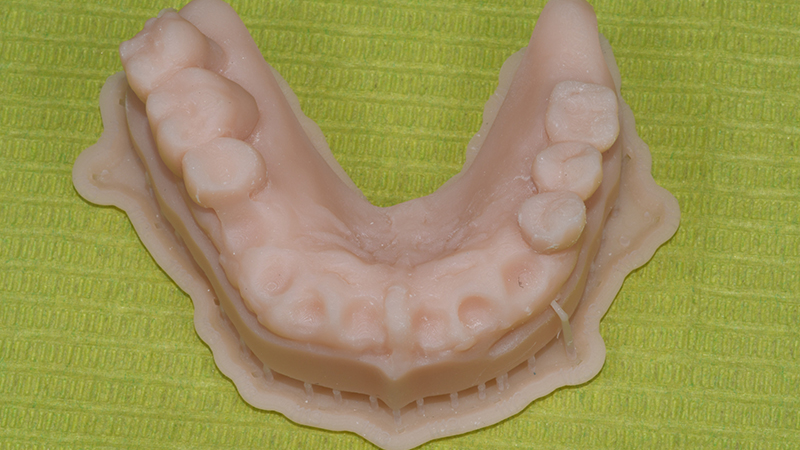

Dopo aver verificato la posizione della dima chirurgica sul modello digitale stampato, quest’ultima è stata posizionata in bocca tramite il supporto dentale dei settori latero-posteriori ed un pin di fissaggio è stato applicato (Anchor Pin Kit, Megagen, Daegu, Corea del Sud) (Figs. 7, 8, 9).

Fig. 7 - Modello digitale stampato

Le fixtures implantari sono state inserite seguendo il planning pre-chirurgico (Figs. 10, 11) in posizione 13-21-23-24. Lo spazio presente tra la componente vestibolare di ciascun impianto e l’osso vestibolare (jumping distance) e gli alveoli post-estrattivi non riceventi impianti, hanno ricevuto l’innesto di sostituto osseo xenogenico collagenato di origine suina (The Graft, Purgo, Challans, Francia) (Figs. 12, 13, 14) dopo aver posizionato i Multi-Unit abutment (MUA). La protesi provvisoria è stata avviata entro 24 ore dal termine della chirurgia (Figs. 15, 16).